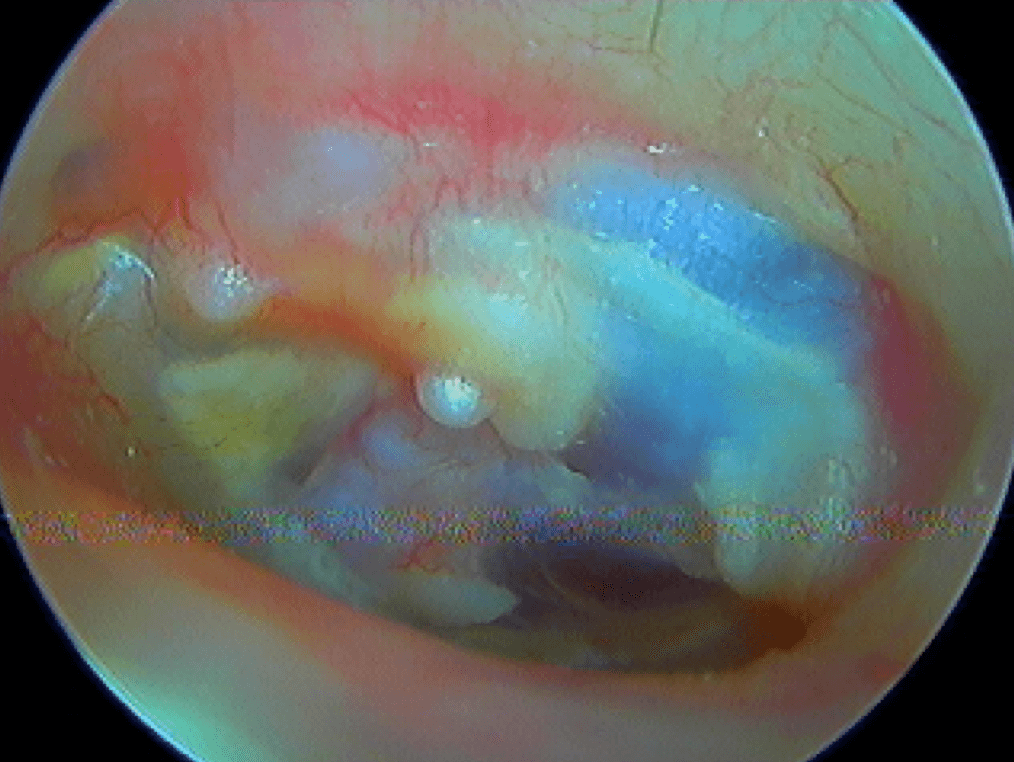

10 CHOLESTÉATOME

10/1 Cholestéatome acquis (secondaire)

Epithélium stratifié, kératinisé et squameux présent dans l’oreille moyenne, "croissance progressive de peau dans l’oreille", "skin in the wrong place": la peau malade du tympan va détruire tout sur son passage: le tympan lui-même, les osselets, le cadre osseux jusqu'à la méninge. Là il faut bien utiliser toutes ses connaissances sémiologiques d'otoscopie pour faire le diagnostic, qui est plus facile que l'otite atéléctasique, en raison de la présence de squames.

Cela touche adultes & enfants.

Le/la patient·e avait attendu quelques mois avant de revenir: le cholestéatome a englobé tout le malléus: